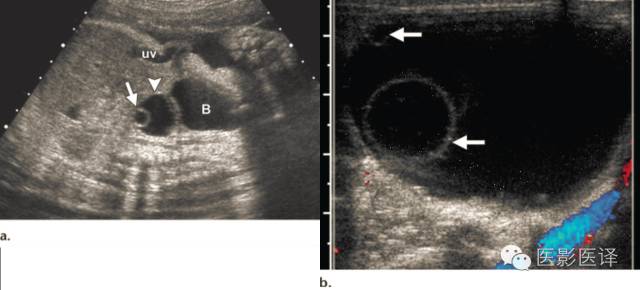

图3:单纯性卵巢囊肿。(a)矢状位胎儿超声图像显示一个边界清楚薄壁腹内囊肿(箭头),其内可见一个子囊(箭)。囊肿位于膀胱(B)上方腹中线区。Uv=脐静脉。(b)同一病人轴位超声多普勒图像显示在薄壁卵巢囊肿中有两个子囊(箭头)

胎儿卵巢囊肿5.6厘米会消失吗,卵巢巨大囊肿与妊娠鉴别